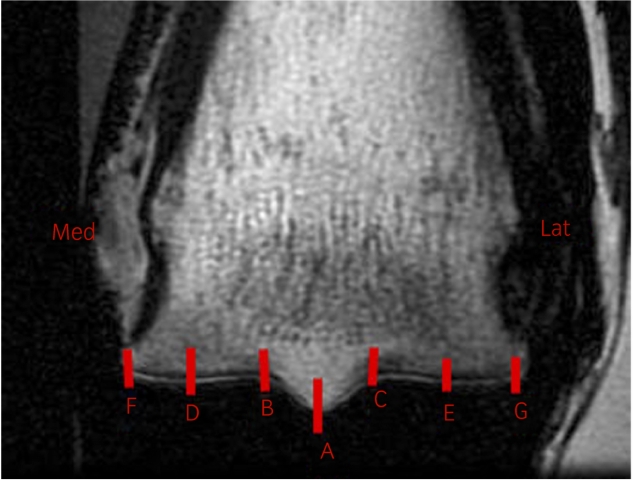

Increases in subchondral bone thickness measured from MRI images were associated with increased fracture risk.

Dr Tim Parkin of Glasgow University Veterinary School explores the question Can we use subchondral bone thickness on high-field magnetic resonance images to identify Thoroughbred racehorses at risk of catastrophic lateral condylar fracture?1 The study, which assessed the bone-level risk factors for fracture in racehorses, is part of long-standing programme of research to prevent racehorse injury, funded by the Horserace Betting Levy Board (HBLB).

A total of 191 MC3s from 96 horses with (47) and without (49) lateral condylar fracture, were subjected to MR imaging. Greater depth of dense subchondral/trabecular bone in the palmar half of the lateral parasagittal groove of distal MC3 was associated with an increased likelihood of being from a horse that had sustained a fracture. The identification of markers for pre fracture change, that can be detected using MRI, suggests that reliable screening methods for fracture risk may be developed. The routine use of such screening programmes would enable the introduction of interventions, such as alterations to training regimens based on known risk factors for lateral condylar fracture that may reduce the likelihood of fracture in susceptible horses.